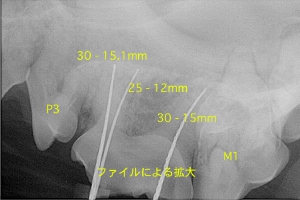

各々の根管にファイルを挿入し根管長を測定

ポータブルレントゲンによる術中写真

術後の写真 充填( 赤ラインは根先部 )

レントゲンでは根先部を斜めから撮影するために上記のように作成したアピカルシートは根先よりおよそ1mmくらい上部(歯冠側)に描出されます。上記は頬側遠心(30 - 15.1mm)、舌側遠心(25 - 12mm )、近心(30 - 15mm)にて形成を終了しております。